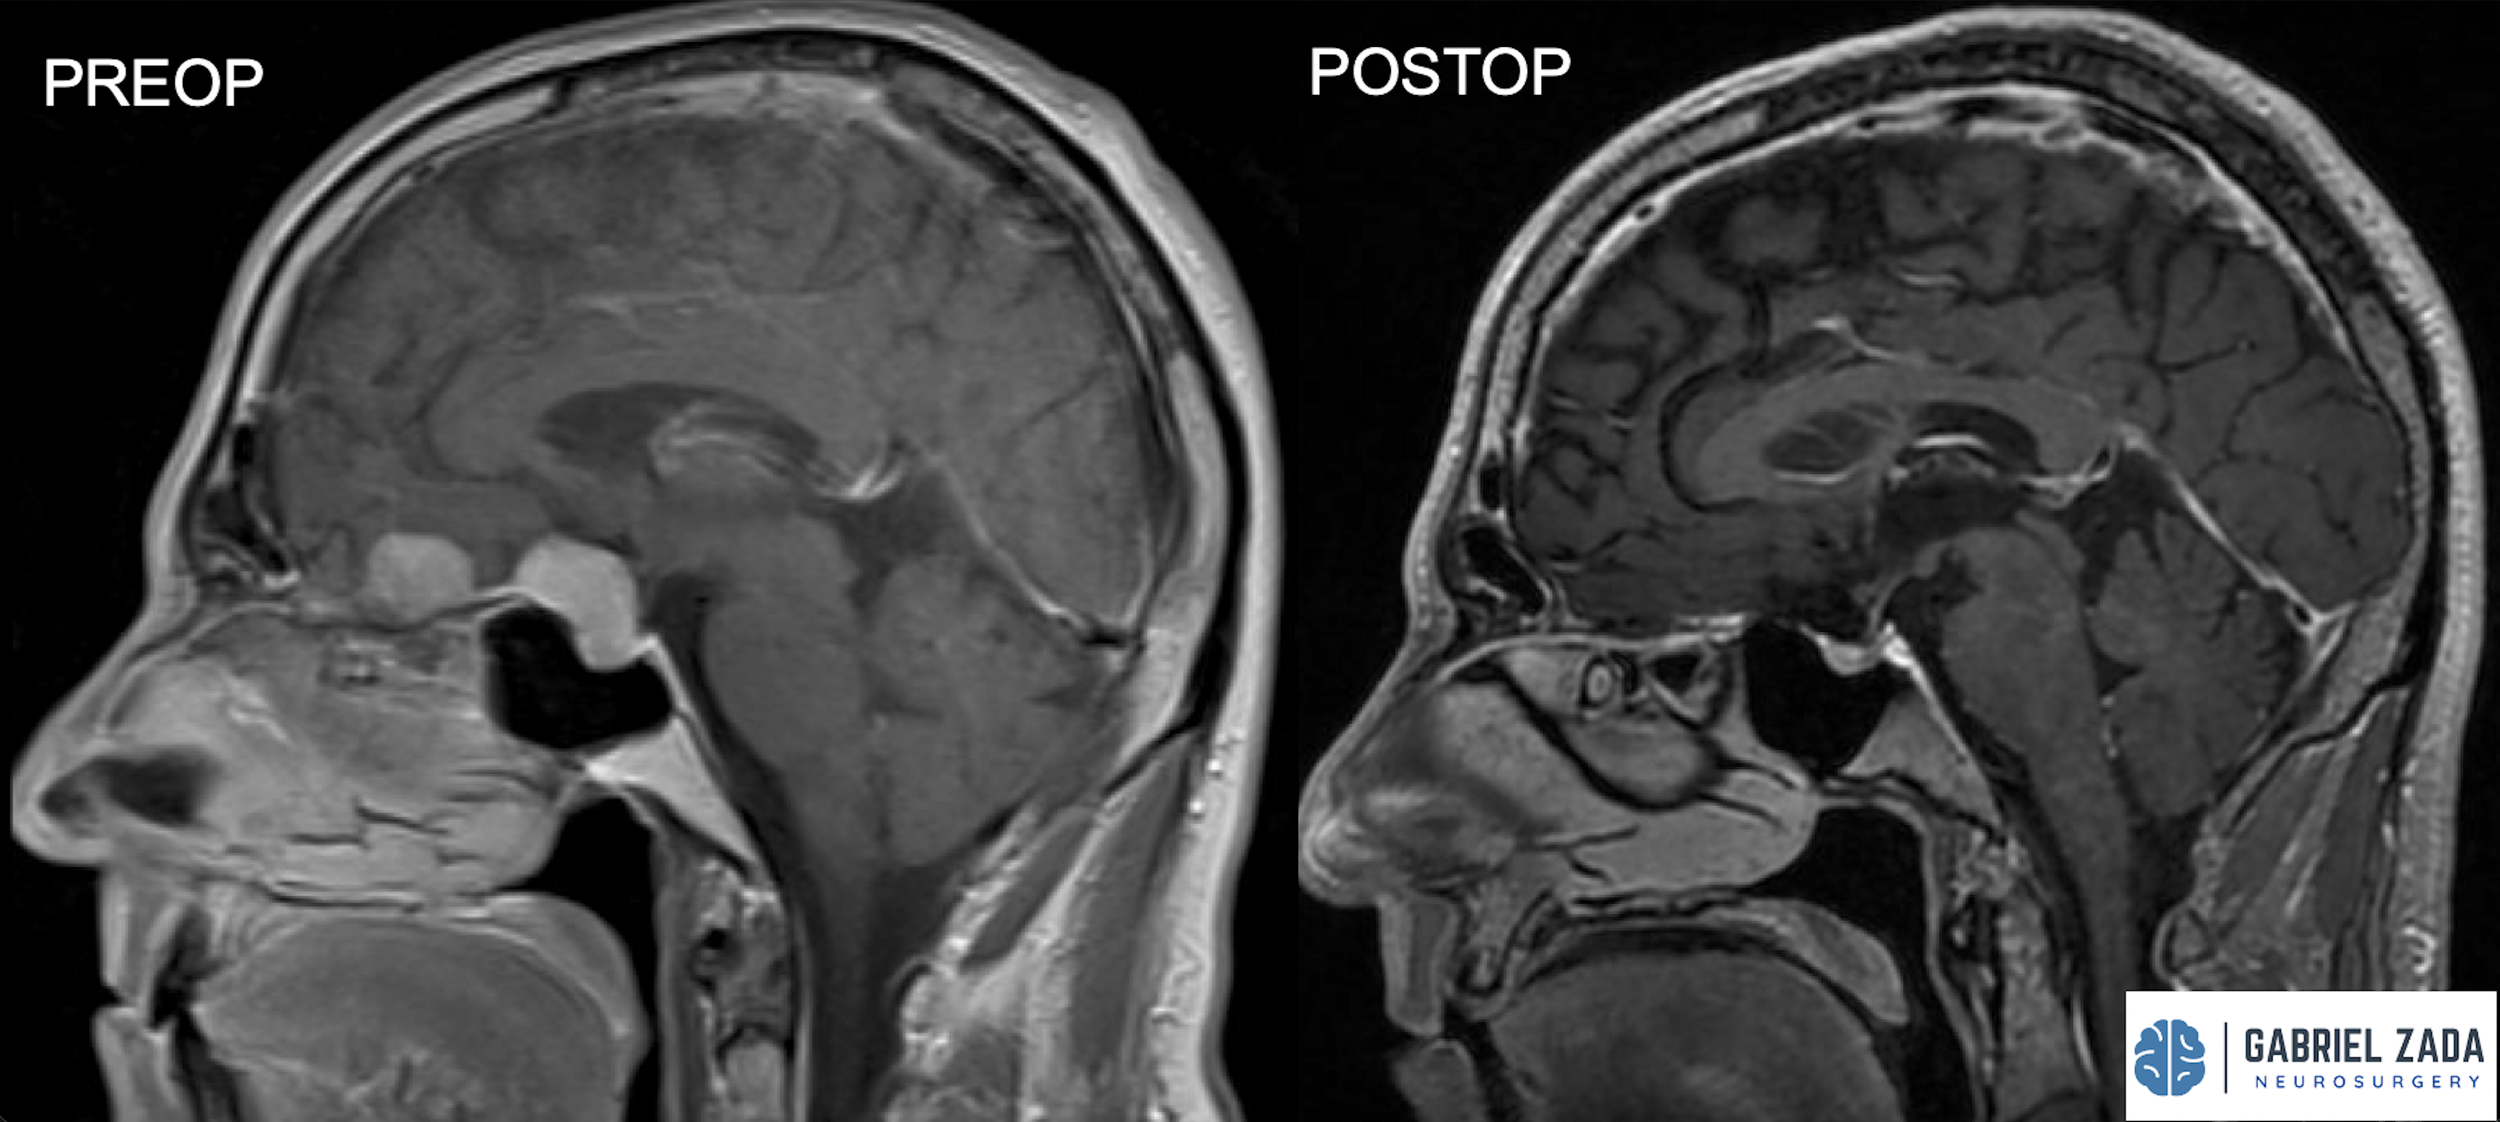

Explore this comprehensive gallery featuring pre‑ and post‑operative imaging of patients with skull‑base tumors treated by Gabriel Zada, MD, MS, FAANS, FACS. These cases highlight Dr. Zada’s expertise in advanced neurosurgical techniques and outcomes.

*Representative cases shown for educational purposes. All images de-identified. Individual results vary.